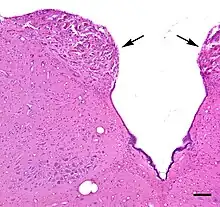

The area postrema is a paired protuberance found at the inferoposterior limit of the fourth ventricle.[1][5] Specialized ependymal cells are found within the area postrema. These cells differ slightly from the majority of ependymal cells (ependymocytes), forming a unicellular epithelial lining of the ventricles and central canal. The area postrema is separated from the vagal trigone by the funiculus separans, a thin semitransparent ridge.[1][5] The vagal trigone overlies the dorsal vagal nucleus and is situated on the caudal end of the rhomboid fossa or 'floor' of the fourth ventricle. The area postrema is situated just before the obex, the inferior apex of the caudal ventricular floor. Both the funiculus separans and area postrema have a similar thick ependyma-containing tanycyte covering. Ependyma and tanycytes can participate in the transport of neurochemicals into and out of the cerebrospinal fluid from its cells or adjacent neurons, glia or vessels. Ependyma and tanycytes may also participate in chemoreception.[1][5]